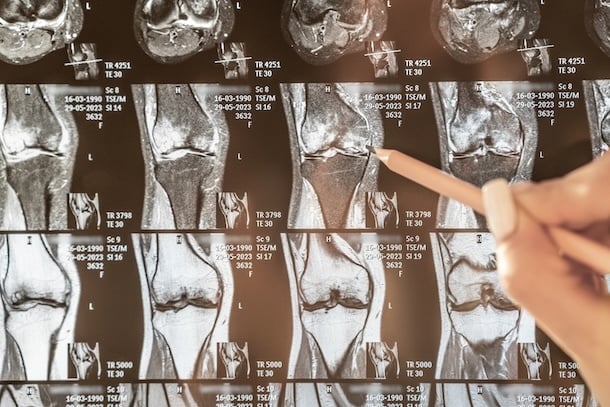

Pruebas de Imagen:

Resonancia Magnética (RM): Es la prueba de imagen más útil para visualizar el estado del cartílago, el grado de desgaste y la presencia de edema (hinchazón).